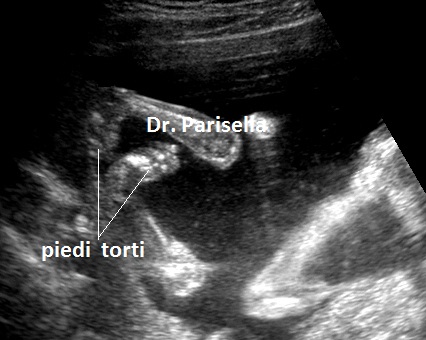

Possono essere presenti: 6) piede torto; 7) idrocefalia.